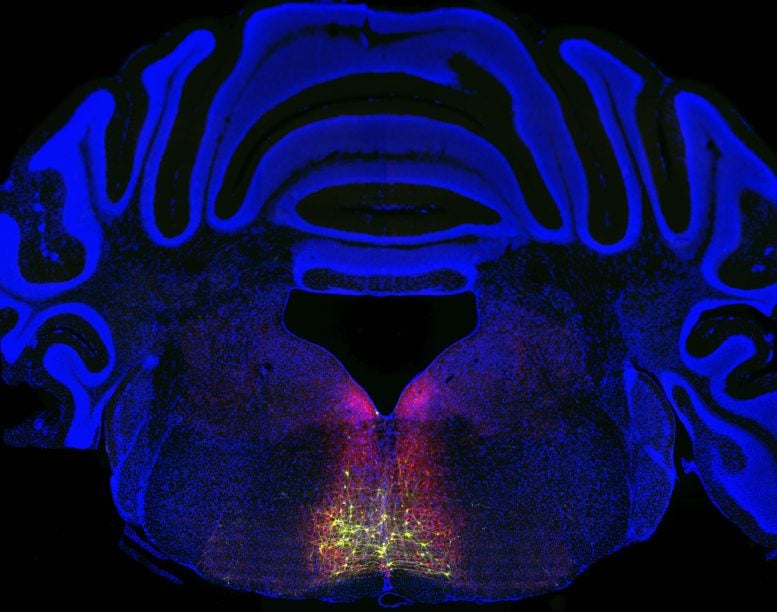

To discover this pathway, Chen’s group began with neurons within the RVM identified to give a contribution to ache sensitization. The usage of genetic labeling ways, they marked attached neurons with a fluorescent protein, revealing a looping circuit that starts within the spinal twine, passes in the course of the thalamus, cortex, and brainstem, and returns to the spinal twine.